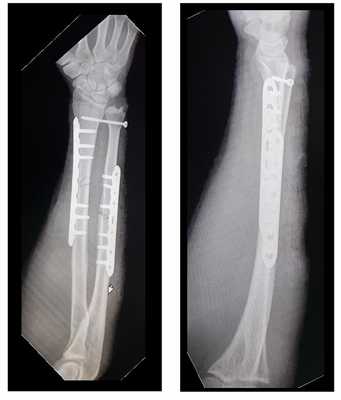

Выполнен остеосинтез обеих костей правого предплечья метафизарными пластинами 3,5 мм, фиксация дистального радио-ульнарного сочленения винтом.

Внешний вид конечности после операции, угловая деформация устранена. Сегмент конечности стабилен, движения в локтевом и лучезапястном суставах не ограничены, ротация предплечья ограничена из-за наличия позиционного винта, который будет удаляться через 6 недель.

Реннтгенограммы после операции.

Такой остеосинтез весьма стабилен и позволяет начать реабилитацию уже через сутки после операции. Форсированные нагрузки на предплечье естественно ограничены до рентгенологического подтверждения консолидации. Рентгенконтроль целесообразно производить через 6 и 12 недель. При хорошо выраженных признаках сращения полная нагрузка возможна через 12 недель после операции.